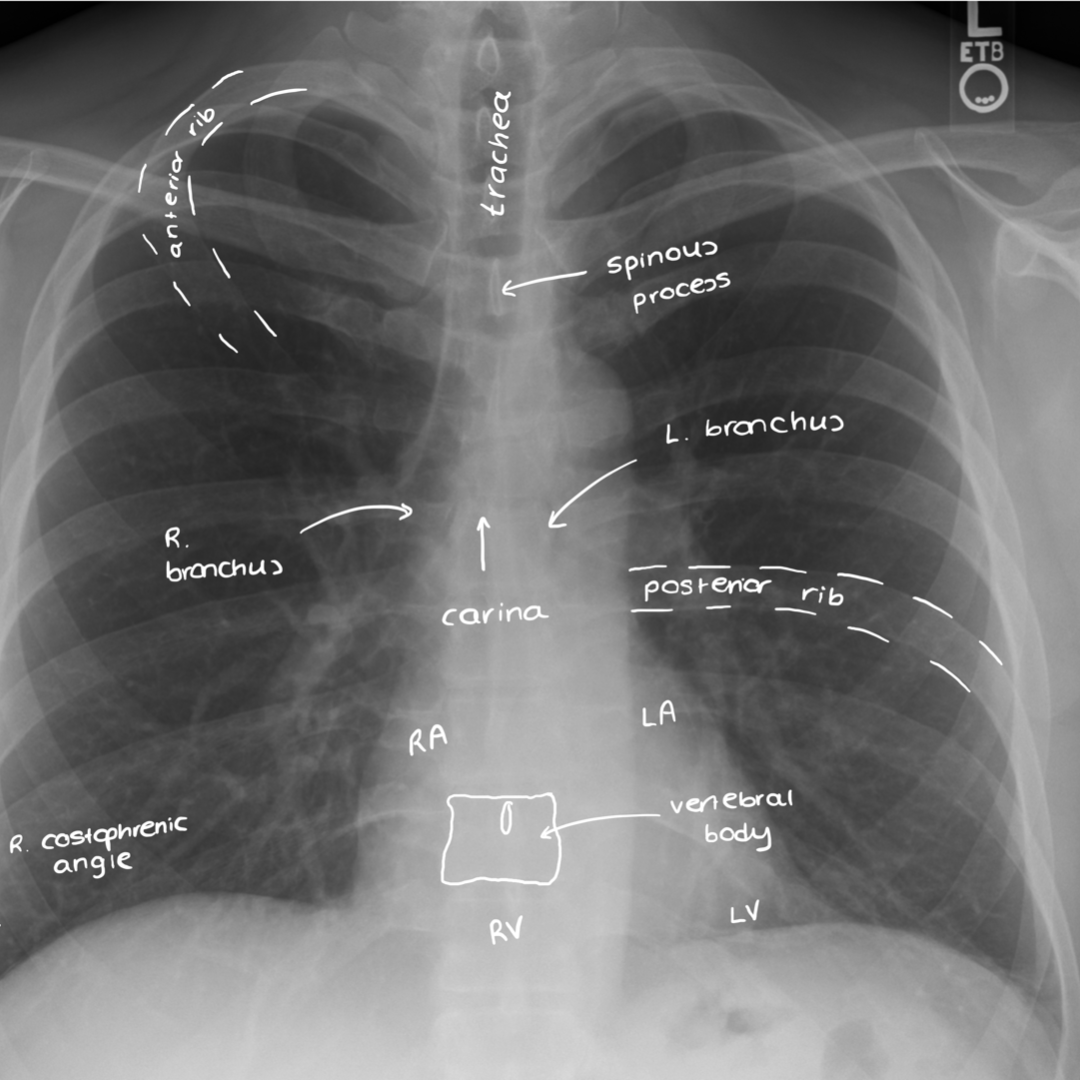

CXR With Labelled Structures

• Rotation: Compare the distance between the heads of the clavicles and the spinous process – are they equidistant? If not, the film is rotated which can make interpretation difficult e.g. assessing deviation of the trachea.

• Inspiration: Should be able to see 6 anterior ribs and 10 posterior ribs for adequate inspiration.

• Penetration: This describes how much the X-rays have passed through the body i.e. penetrated. Can you see the vertebral bodies behind the heart? If not, the x-ray is likely under-penetrated.